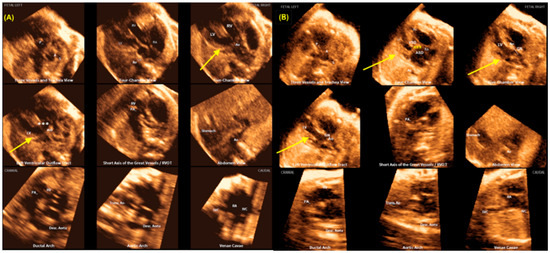

- Yeo, L.; Romero, R. Fetal Intelligent Navigation Echocardiography (FINE): A Novel Method for Rapid, Simple, and Automatic Examination of the Fetal Heart. Ultrasound Obstet. Gynecol. 2013, 42, 268–284. [Google Scholar] [CrossRef]

- Carrillo, M.C.; Rolo, L.C.; Tonni, G.; Araujo Júnior, E. Evaluation of the quality of standard fetal heart views using the FAST, STAR and FINE four-dimensional ultrasound techniques in congenital heart disease screening. Echocardiography 2020, 37, 114–123. [Google Scholar] [CrossRef]

- Yeo, L.; Romero, R. Color and power Doppler combined with Fetal Intelligent Navigation Echocardiography (FINE) to evaluate the fetal heart. Ultrasound Obstet. Gynecol. 2017, 50, 476–491. [Google Scholar] [CrossRef]

| FINE (“5D heart”) | Intelligent navigation Automated reconstruction of the 9 planes of fetal echocardiography Reduce examination time Tele-medicine assistance | Availability of 3DUS machines with FINE software Unfavorable fetal statics and maternal obesity |